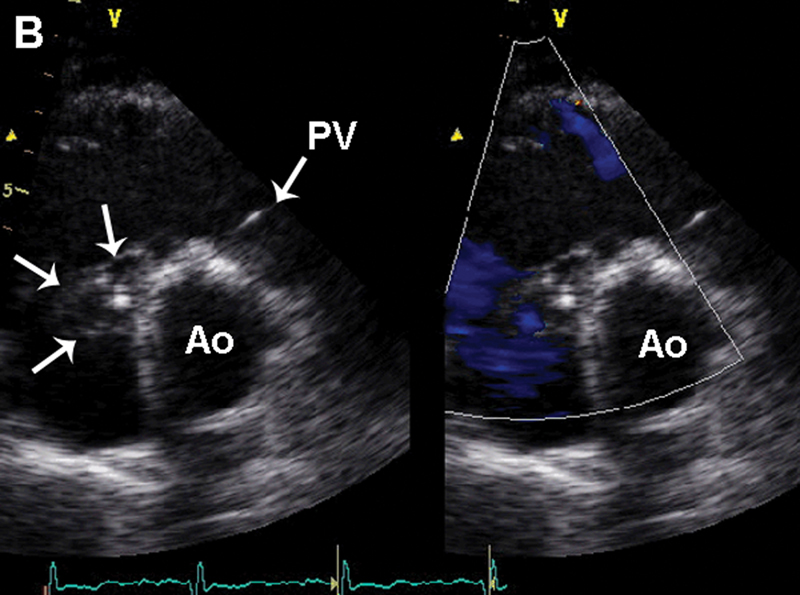

فحوصات تشخيصية لبعض امراض القلب والشرايين التاجية